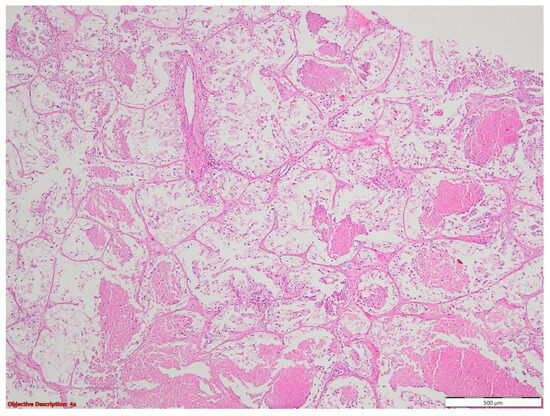

3.1. Case No. 1

3.2. Case No. 2

3.3. Case No. 3

3.4. Case No. 4